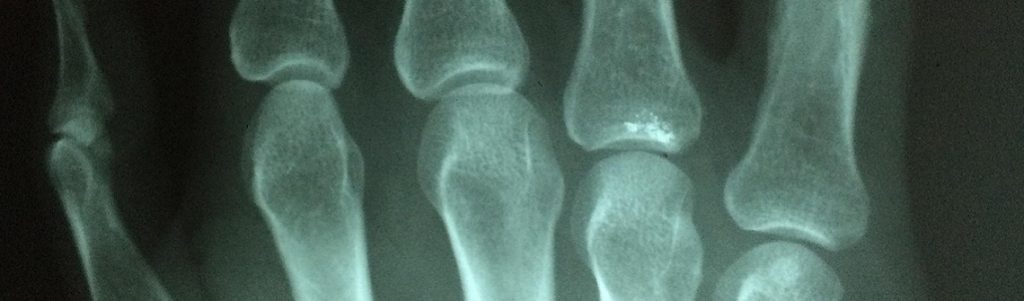

Un nanocomposite biodégradable et imprimable en 3D, pour la greffe osseuse

L’impression 3D est désormais utilisée en routine dans certaines chirurgies orthopédiques et maxillo-faciales pour des greffes complexes. Cette technologie est même en train de révolutionner le domaine de la chirurgie reconstructive, grâce au développement de nouveaux biomatériaux. [Lire plus…]